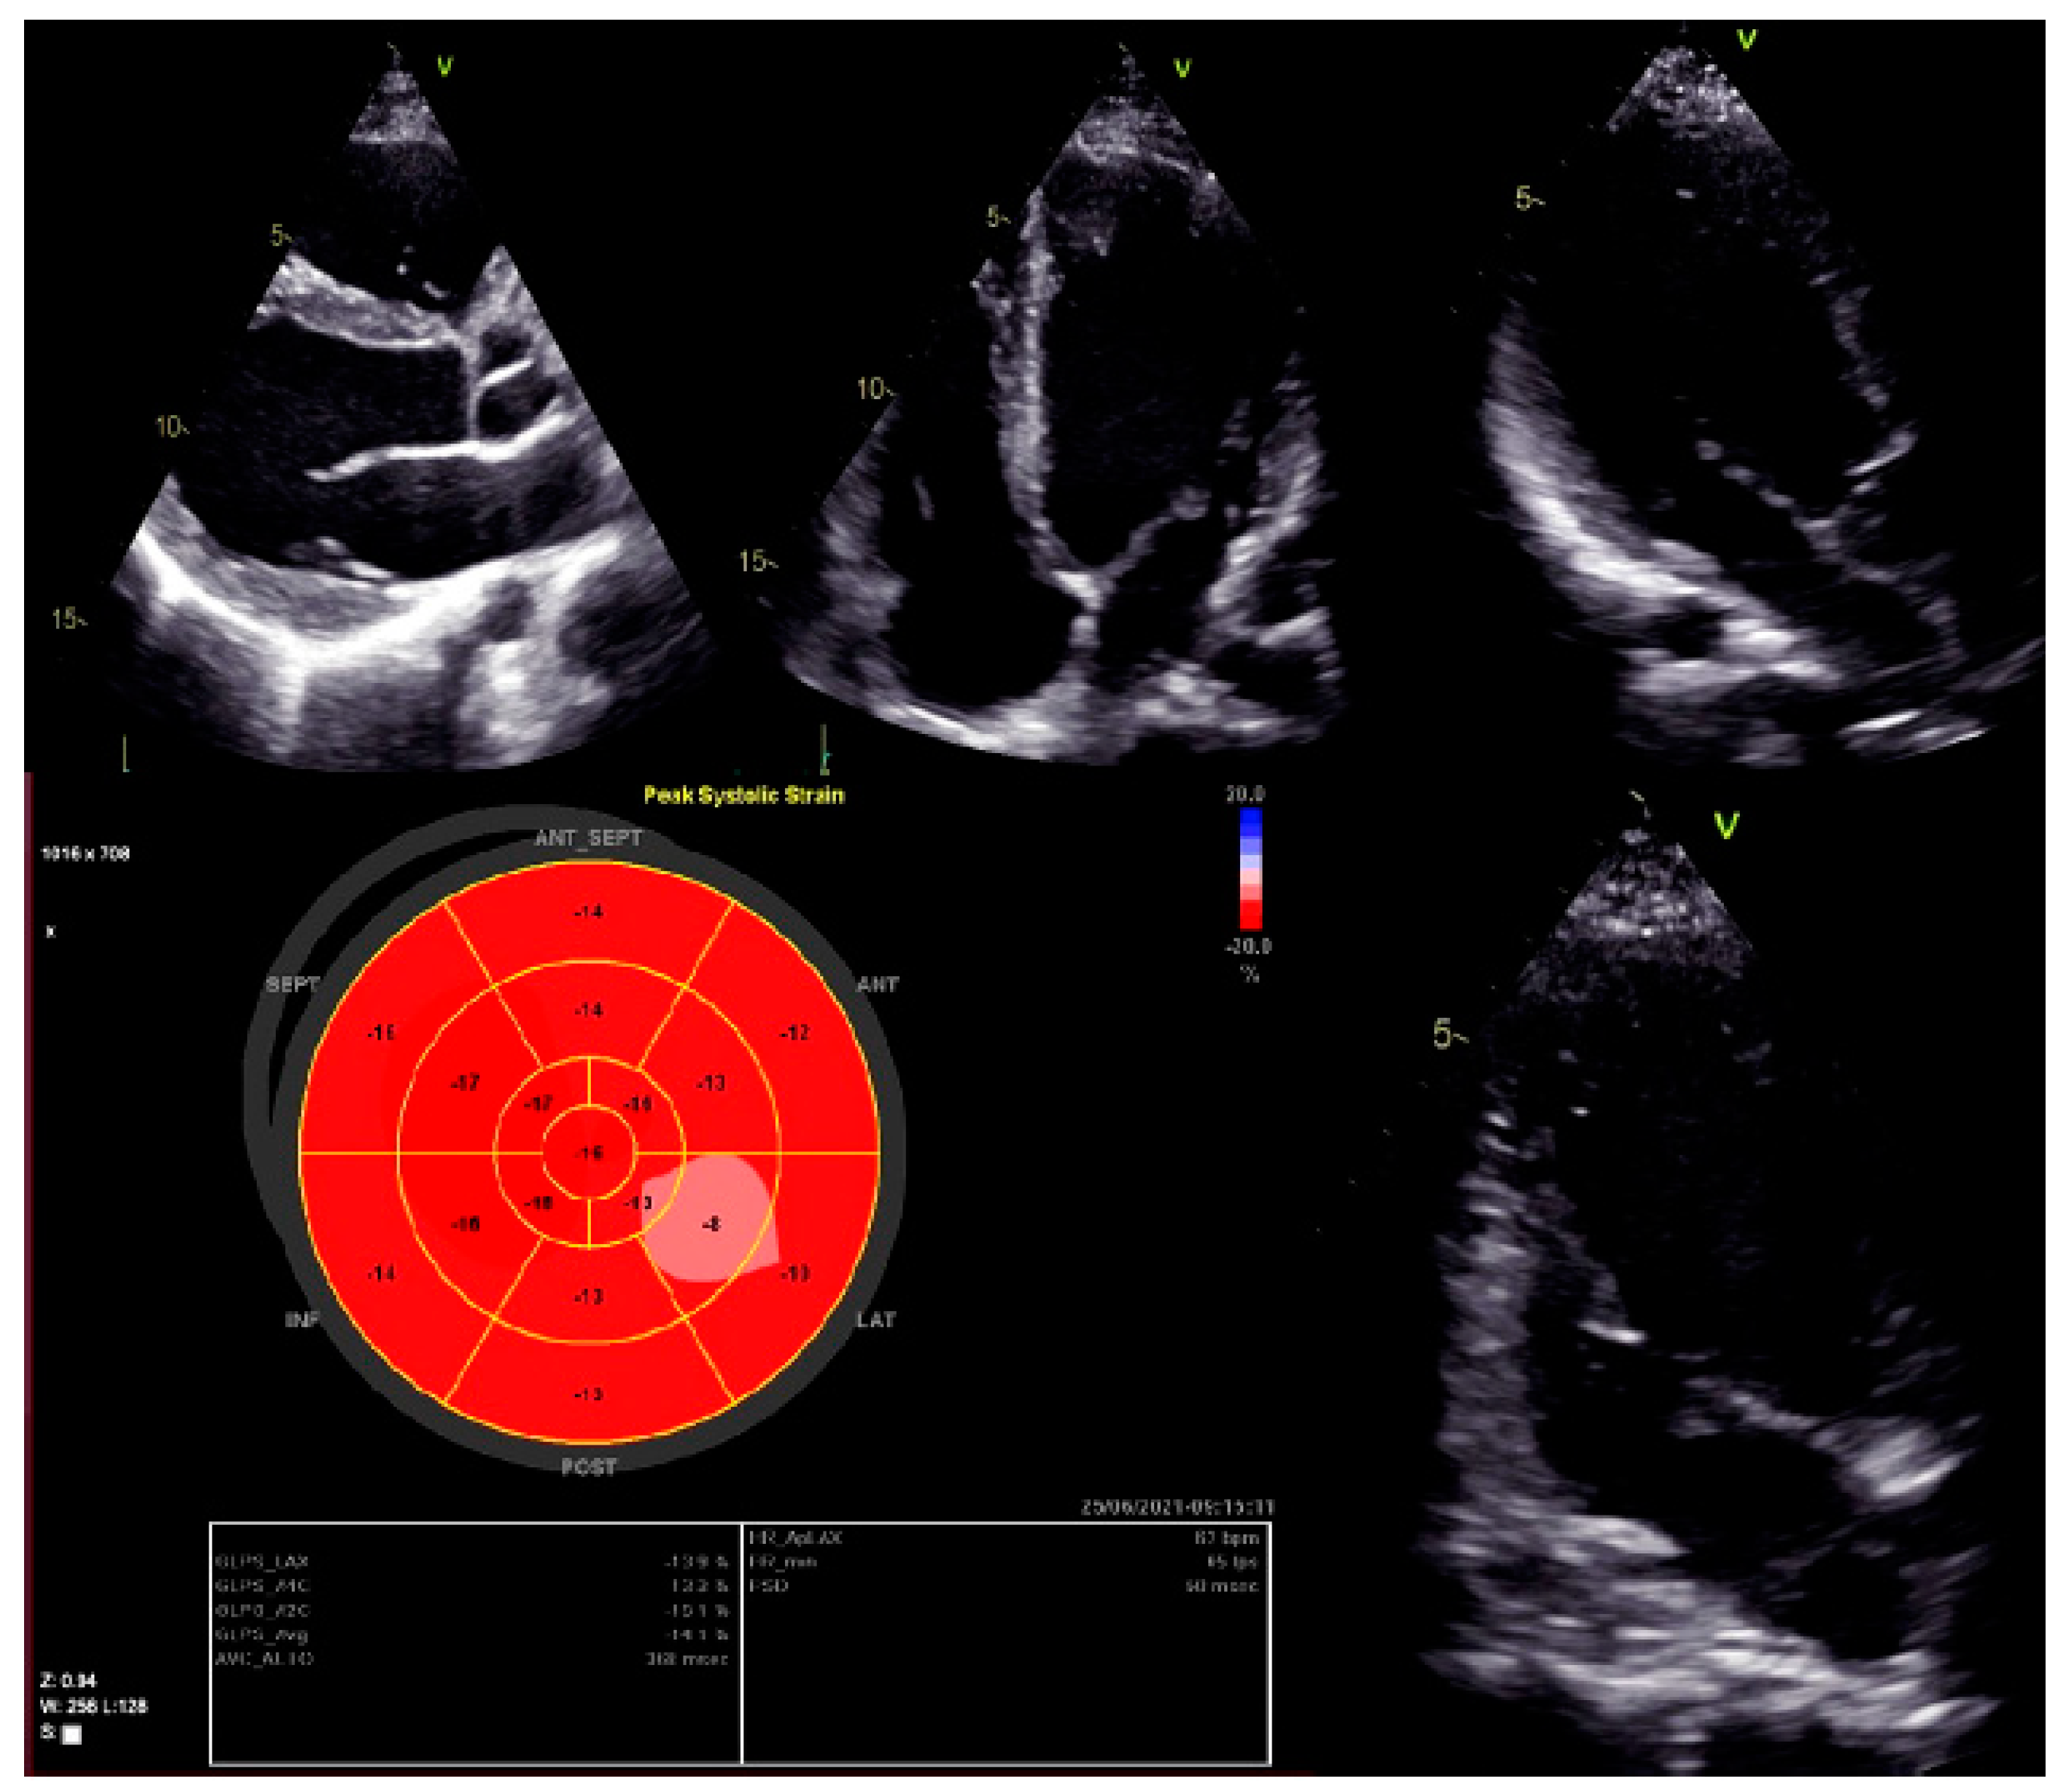

Moreover, dilated LV with decreased systolic function and global longitudinal myocardial strain were found in cardiac 2D TTE (transthoracic echocardiography) (Figure 2). Magnetic resonance imaging did not find myocardial fibrosis by LGE (late gadolinium enhancement), T1 and T2 mapping, and confirmed changes found on echocardiography (Figure 3).

Figure 2.

Left ventricular global longitudinal strain by speckle-tracking echocardiography.

Thus, the results of most studies suggest that DCM caused by pathogenic variants of the BAG3 gene detected at a young age is associated with rapid disease progression, life-threatening arrhythmias, poor prognosis, and survival. In our case, the patient was also young, 22 years of age at diagnosis, and an event recorder was implanted due to the risk of severe arrhythmias. Although our patient has been stable for three years, close monitoring is continued every year (dynamics of cardiac structure and function assessed by echocardiography and CMR at baseline and 1 year follow up are presented in Table 2) due to the high risk of sudden cardiac death.

Dynamics of cardiac structure and function assessed by 2D echocardiography and CMR at baseline and after 1 year.